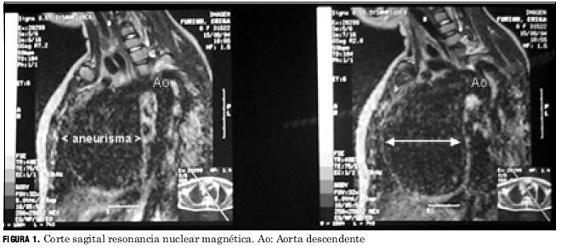

Se efectúan angio resonancia magnética (Fig.1) y tomografía axial computarizada que confirman el diagnóstico y descartaron signos de disección aguda, trombos intraluminales y la presencia de dilataciones en otros sectores vasculares. Las medidas del saco aneurismático fueron aproximadamente de 95 y 115 mm para ambas técnicas respectivamente.

Tanto las medidas obtenidas por angio resonancia magnética y tomografía axial computarizada fueron mayores que las obtenidas mediante el estudio ecocardiográfico siendo la tomografía quien más se aproximó a la medida directa intraoperatoria.